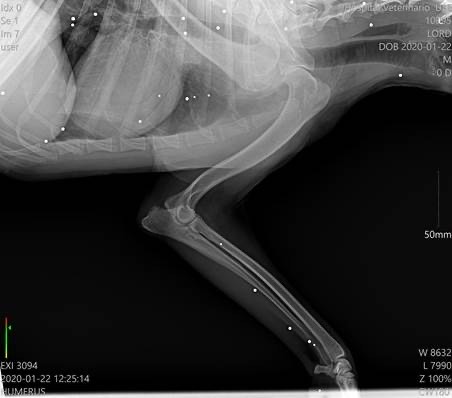

Der kleine Kerl begann zu humpeln und nach weiteren Untersuchungen sowie dem Besuch bei einem Spezialisten, wurde festgestellt, dass er unzählige Schrotkugeln im Körper hat und Arthrose in diversen Gelenken.Lord wird leider zukünftig auf Schmerzmedikamente angewiesen sein.

Der kleine Kerl begann zu humpeln und nach weiteren Untersuchungen sowie dem Besuch bei einem Spezialisten, wurde festgestellt, dass er unzählige Schrotkugeln im Körper hat und Arthrose in diversen Gelenken.